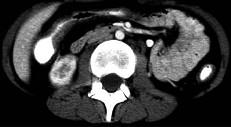

问题 女,32岁,腹痛、腹泻、便秘交替出现,粘液血便半年,里急后重,影像检查如图,最佳的诊断是 ( )

选项 A.结肠癌 B.慢性结肠炎 C.过敏性结肠炎 D.溃疡性结肠炎 E.肠结核

答案 D